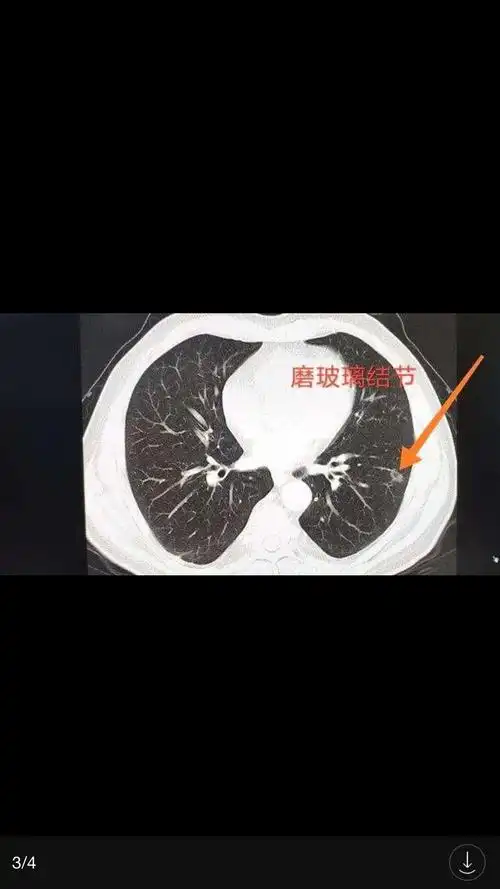

少见良性肺结节ct表现影像天地

肺部多发磨玻璃结节良性多 肺磨玻璃结节怎么治疗?-图片大观-奇异网